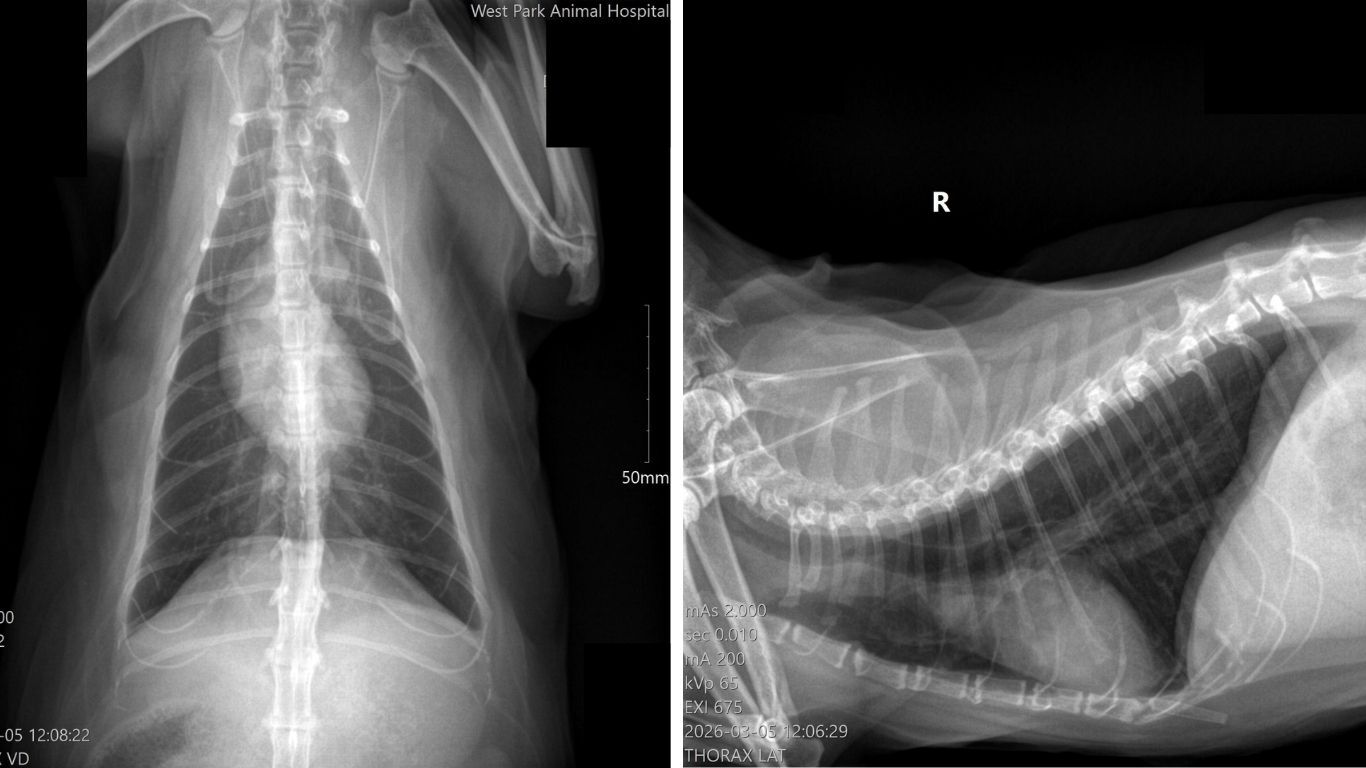

1. Chest X-Rays

Chest radiographs help us evaluate:

- Overall heart size and shape

- Blood vessels in the lungs

- Any signs of fluid buildup related to heart disease